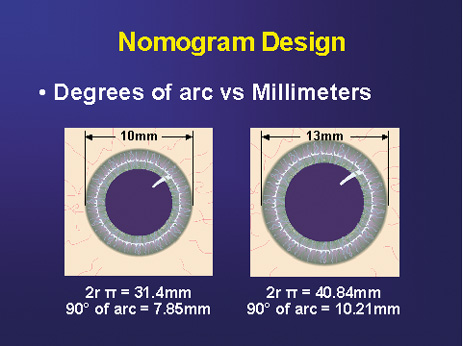

All incisions are paired, except in the case of very low ATR astigmatism

wherein a single 35-degree nasal LRI is placed opposite to the single-plane

temporal clear-corneal phaco incision. Paired incisions are preferred

to optimize symmetric corneal flattening and are expressed in

degrees of arc rather than chord length. This is done in order to diminish

over- and undercorrections for unusually small or large corneas, because

corneal diameter may significantly impact the relative length

of the arcuate incision and its resultant effect (Fig. 3). This nomogram, which has been designed specifically for the cataract

Fig. 3. Nomogram design. Note relative disparity in incision length between a large

and small corneal diameter if measured in millimeters. Degrees of

arc lend consistency irrespective of corneal size. (Reprinted from

Hardten DR, Lindstrom RL, Davis EA. Phakic Intraocular Lenses: Principles

and Practice. Thorofare, NJ: SLACK Incorporated, 2004, with permission.) Fig. 3. Nomogram design. Note relative disparity in incision length between a large

and small corneal diameter if measured in millimeters. Degrees of

arc lend consistency irrespective of corneal size. (Reprinted from

Hardten DR, Lindstrom RL, Davis EA. Phakic Intraocular Lenses: Principles

and Practice. Thorofare, NJ: SLACK Incorporated, 2004, with permission.)